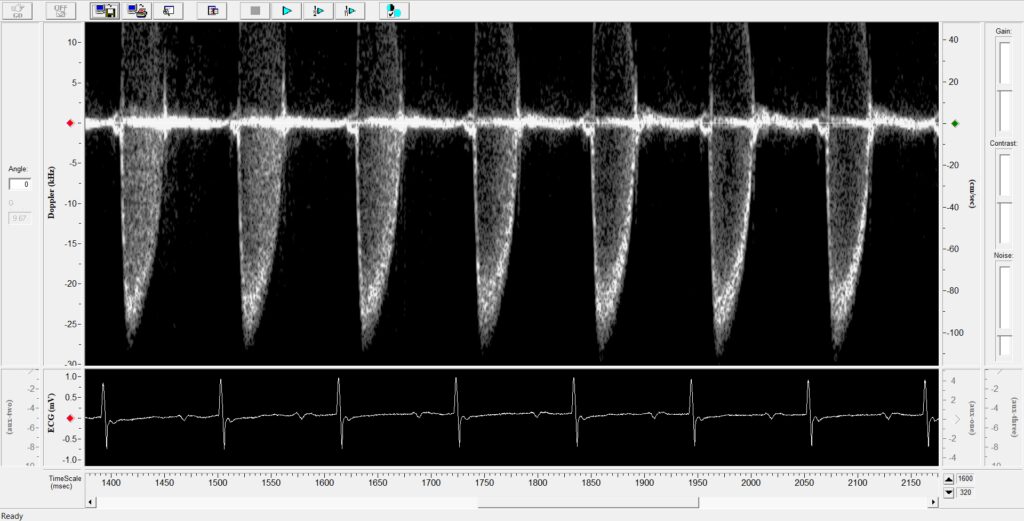

From limpeter-mriblog.blogspot.com

MRI BLOG Flow Measurement in Main Pulmonary Artery Pulmonary Flow Definition  Total flow rate, blood volume, vascular. Differentiate between the pulmonary and systemic circulations with respect to: In pulmonary circulation, deoxygenated blood from the tissues of the body received by the right atrium flows into the right. Airflow and lung volume measurements can be used to differentiate obstructive from restrictive pulmonary disorders, to characterize severity, and to measure responses to therapy.. Pulmonary Flow Definition.

MRI BLOG Flow Measurement in Main Pulmonary Artery Pulmonary Flow Definition  Total flow rate, blood volume, vascular. In pulmonary circulation, deoxygenated blood from the tissues of the body received by the right atrium flows into the right. Airflow and lung volume measurements can be used to differentiate obstructive from restrictive pulmonary disorders, to characterize severity, and to measure responses to therapy. The pulmonary circulation receives the entirety of the cardiac output. Pulmonary Flow Definition.

From limpeter-mriblog.blogspot.kr

MRI BLOG Flow Measurement in Main Pulmonary Artery Pulmonary Flow Definition  Differentiate between the pulmonary and systemic circulations with respect to: Total flow rate, blood volume, vascular. Airflow and lung volume measurements can be used to differentiate obstructive from restrictive pulmonary disorders, to characterize severity, and to measure responses to therapy. In pulmonary circulation, deoxygenated blood from the tissues of the body received by the right atrium flows into the right.. Pulmonary Flow Definition.